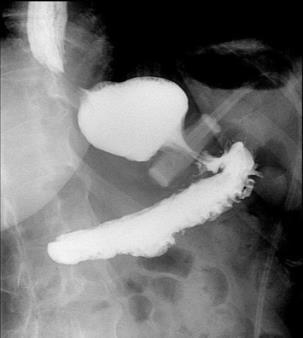

CASE PRESENTATION: A 67-year-old male with a history of partial liver resection, peptic ulcer disease, and Helicobacter pylori gastritis s/p quadruple therapy presented with acute on chronic abdominal pain despite being on a proton pump inhibitor (PPI). He had abdominal pain for the past 5 years associated with nausea, vomiting, diarrhea, and a 50-pound unintentional weight loss. An esophagogastroduodenoscopy (EGD) six months ago demonstrated peptic ulcer disease and Helicobacter pylori which was successfully eradicated.

He underwent a CT-abdomen/pelvis with intravenous contrast in the emergency department which revealed an enhancing 3.4 cm mass in the head of the pancreas with retroperitoneal lymphadenopathy. MRI of the abdomen confirmed the presence of a 3.2 cm enhancing pancreatic head mass with direct extension into the second portion of the duodenum and multiple enlarged retroperitoneal lymph nodes. EGD was remarkable for edema and granularity in the first portion of the duodenum. Endoscopic ultrasound (EUS) was notable for a hypoechoic and heterogeneous irregular mass in the pancreatic head measuring 25 mm by 23 mm in maximal crosssectional diameter with invasion into the serosa and muscularis mucosa of the duodenum. Fine needle aspiration of the pancreatic mass for cytology revealed a well-differentiated pancreatic neuroendocrine tumor (Ki-67 index <1%). Gastrin levels were ordered. He presented again to the hospital 3 weeks later with worsening epigastric abdominal pain and nausea despite adhering to PPI therapy. CT-abdomen revealed new proximal duodenal ulcerations. Gastrin level from the prior admission was noted to be 1988 pg/mL. He subsequently underwent a Whipple's procedure with no complications and was discharged home with a planned EGD surveillance in 6 months.

CONCLUSION: Establishing a diagnosis of ZE can be difficult due to the lack of consistent diagnostic criteria, the widespread use of PPIs that masks mask the symptoms and limited access to gastric pH testing. In our case, the diagnosis was based on a fasting serum gastrin level, FNA results, and imaging findings. Owing to its variable clinical presentation, high mortality, and challenging primary lesion identification, clinicians should consider ZE in the differential diagnosis of patients who are symptomatic despite taking PPI, having Helicobacter pylori successfully eradicated or having multiple duodenal and gastric ulcers that fail to respond to therapy.

Figure 1: CT Abdomen and Pelvis with contrast showing a suspicious mass in the second portion of the duodenum/pancreatic head.